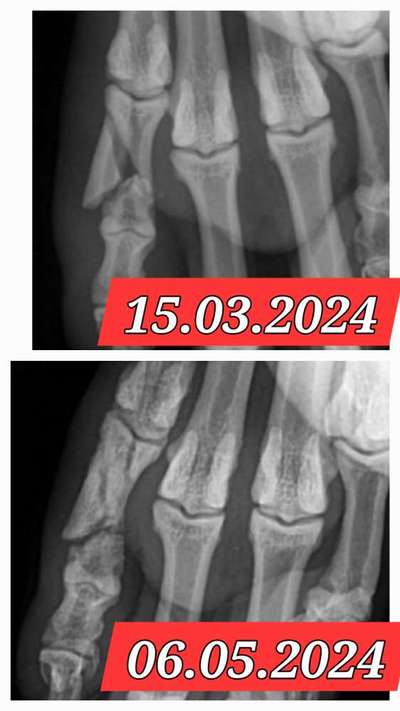

Amy hatte auch ein Traumata mit der Krallenschere. Bin auf Krallenschleifer umgestiegen und heilfroh, dass es total entspannt klappt. Habe es sehr kleinschrittig auftrainiert und klappt hervorragend. Auch das Leben der Kralle wie Amy seit einem Bruch eine Fehlstellung hat ist normalisiert.

Hier noch die Problemkralle nach monatelangem Verband